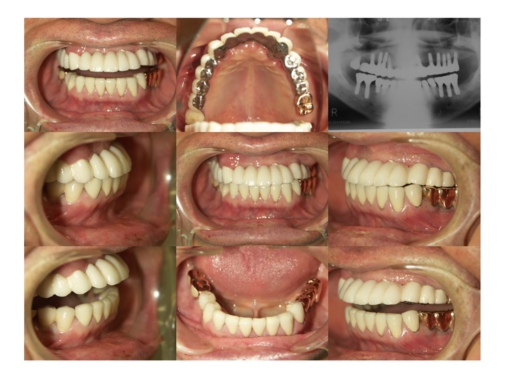

インプラントの症例集

当院で治療された方々の症例を

各科目ごとにご紹介します。